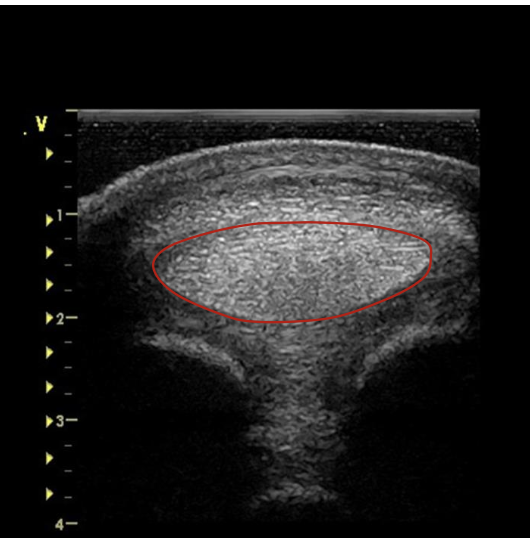

how do the medial and lateral branches of the suspensory ligament appear on transverse scan?

both initially start as oval but then become tear drop as the move distally